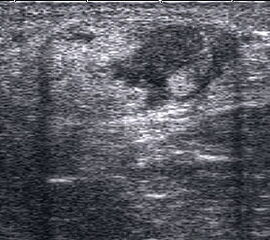

Tenosynovialitis

Eine Tenosynovialitis, hier im Bereich des Os metatarsale I stellt sich als echoarmer Ring (Flüssigkeit) um die echoreiche Sehne dar.

Abbildung 50

Lagerung: Rückenlage.

Schnittführung: Ventraler LS und TS über dem OSG, hinter dem Innen- bzw. Außenknöchel und den Metatarsalia.

Referenzstrukturen: In Abhängigkeit von der Lokalisation Innenknöchel, Fibulaspitze, dorsaler Mittelfuß, Sehnen.

Befunde: Ein echoarmer Ring um die echogene Sehne ist Ausdruck der Flüssigkeitsumscheidung. Bei entzündlicher Ursache auf dem Boden einer rheumatologischen Erkrankung kommt es im zeitlichen Verlauf zum Übergang in eine chronische Tendinopathie. Durch Verklebungen mit dem Sehnengleitgewebe kann das Gleiten der Sehne behindert sein.